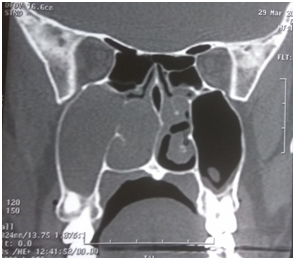

Myers reported cases with intranasal injection of corticosteroids with complete regression of the polyp in few cases, and partial regression in large number of patients. He advocated the use of repeated injections of steroid into the polyp and concluded this method is very useful in patients where surgery need to be avoided.12 Intranasal injections is not a routine practice now; instead steroid preparations are used most commonly as nasal spray or drops, and sometimes systemically. A short course of oral steroid followed by intranasal steroid spray can significantly reduce the nasal polyp, at times complete regression (Figure 4) & (Figure 5). Topical steroids have been investigated extensively. In all patients the addition of simple saline nasal douche for cleaning the nose prior to topical medications is beneficial, as these irrigations have been shown to improve nasal mucocilliary clearance.13

Figure 4 CT scan of a patient with bilateral nasal polyp (before treatment).

Figure 5 CT scan of patient in figure 4, after a short course of oral steroid and follow up intranasal steroid spray.